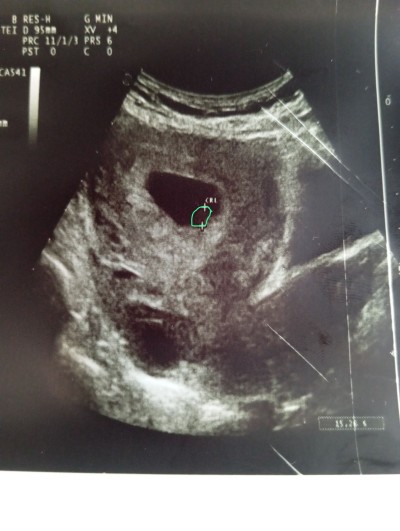

Kızlar merhaba ikiz gebelik olma ihtimali var mı acaba çok merak ediyorum doktor bişey demedi lütfen yardımcı olunnn

Gebelik haftası 8+2

Alttaki için soruyorsanız eğer o kist olabilir. Kese olsa soylerdi

Doktor söylerdi ikinci bir kese olsa ben 6 haftalık gittim bebeğin kalp atışını duyduk ama keseye benzeyen bir yapı daha var 10 gün sonra tekrar gel dedi  yarın randevum var 8 haftalık olduk inşallah ikizdir ultrason da 2. Kese görünüyor

Bu ultrasonu doktor gördü zaten o daha iyi bilir bacım iki kese gözüküyor derdi ama bana kese gibi gelmedi idrar torbası olabilir mi

3.gebeligim 7+1 günlük ve geçen hafta gittimde benimde doktorum gördüm ve hamilelikte oluşan kist Lee oluşuyormus aynı buna benziyor zararsız dedi